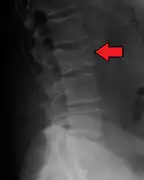

The diagnostic examination of a person with suspected multiple myeloma typically includes a skeletal survey. This is a series of X-rays of the skull, axial skeleton, and proximal long bones. Myeloma activity sometimes appears as "lytic lesions" (with local disappearance of normal bone due to resorption). And on the skull X-ray as "punched-out lesions" (pepper-pot skull). Lesions may also be sclerotic, which is seen as radiodense.[48] Overall, the radiodensity of myeloma is between −30 and 120 Hounsfield units (HU).[49] Magnetic resonance imaging is more sensitive than simple X-rays in the detection of lytic lesions, and may supersede a skeletal survey, especially when vertebral disease is suspected. Occasionally, a CT scan is performed to measure the size of soft-tissue plasmacytomas. Bone scans are typically not of any additional value in the workup of people with myeloma (no new bone formation; lytic lesions not well visualized on bone scan).

Pathological fracture of the lumbar spine due to multiple myeloma -